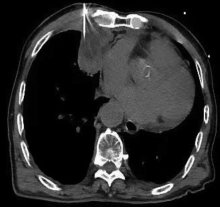

Yamamoto N, Watanabe T, Yamada K, et al. Efficacy and safety of ultrasound (US) guided percutaneous needle biopsy for peripheral lung or pleural lesion: comparison with computed tomography (CT) guided needle biopsy[J]. J Thorac Dis, 2019, 11(3): 936-943. DOI: 10.21037/jtd.2019.01.88.

Jarmakani M, Duguay S, Rust K, et al. Ultrasound versus computed tomographic guidance for percutaneous biopsy of chest lesions[J]. J Ultrasound Med, 2016, 35(9): 1865-1872. DOI: 10.7863/ultra.15.10029.